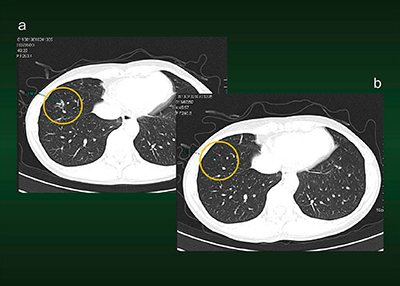

症例3は,58歳,男性。肺がん検診のためのCTにて右のS5胸壁に接して結節性の病変が認められた(図4 a)。体積が自動計測で表示されており,半年後に経過観察画像の計測結果と比較したところ,やや大きくなっていた(図4 b)。この時点で専門医に紹介したが,半年間の経過観察の結果,炎症性の変化と診断され,現在は当クリニックにて毎年1回健診を行っている。この症例でも,病巣をマーキングしておけば,すぐに過去と現在の画像が並列表示されるため,経時的比較には非常に有用である(図5)。

syngo.viaの経時的比較における課題としては,CT画像は4回前の検査分まで並列表示可能で,表示そのものは簡単に行えるが,過去のバージョンアップ時に病巣抽出のための閾値が変更されているため,過去画像でのAuto Segmentationの再測定を行わなければならないことである。また,次回の検査でスムーズに比較するためには所見を整理しておく必要があり,所見数が多いと整理に時間がかかってしまうことも,課題として挙げられる。

図4 症例3:Auto Segmentationによる病変の測定・認識

図5 症例3:Auto Segmentationにおける過去・現在画像の並列表示